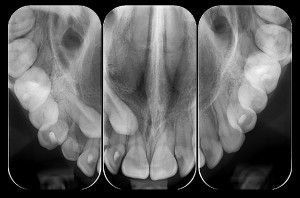

– Radiografia Oclusal